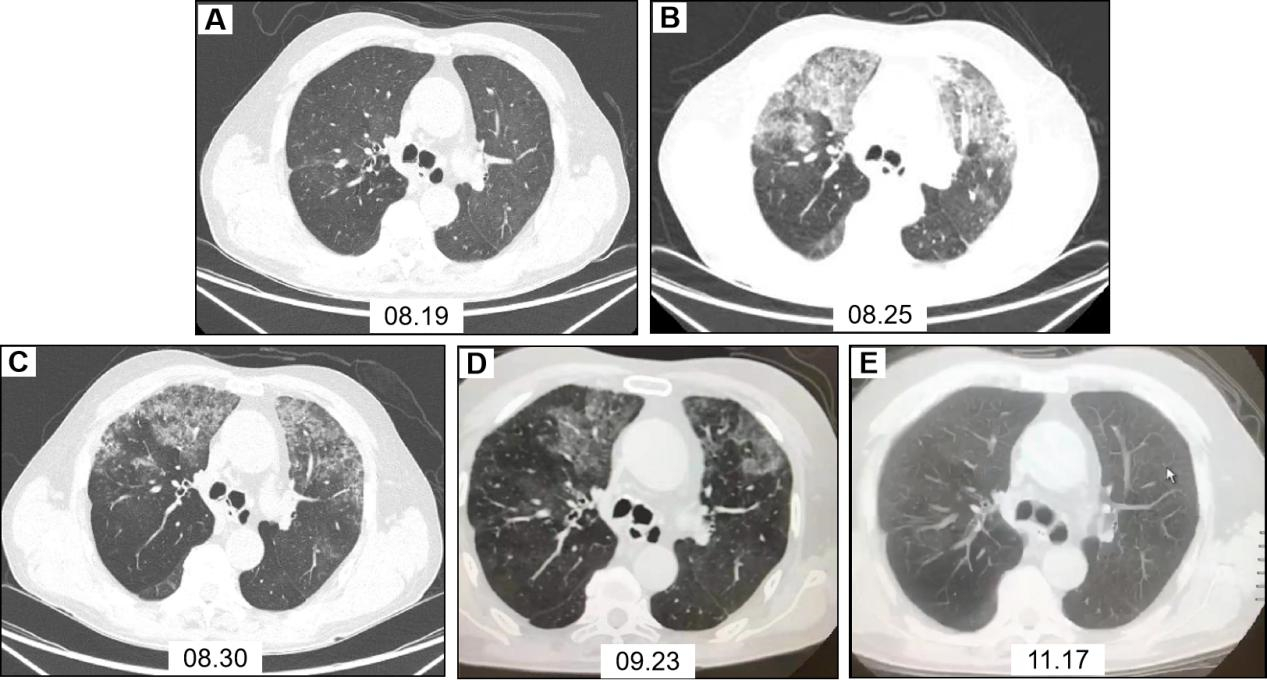

患者,男,64岁,2020-08-19因“胸闷4 d,加重11 h”入院。患者4 d前受凉后出现活动后胸闷、气喘,间断咳嗽、咳痰,于家中自行静脉应用抗感染、舒张支气管、化痰等药物治疗。11 h前误将石蜡油20 mL静脉注射,立即出现持续性胸闷、气喘,剧烈咳嗽,持续约20 min后症状较前稍减轻,至“漯河市中心医院”就诊,给予对症治疗(具体不详),症状无明显减轻,遂来本院。入院查体:体温36.5℃,脉搏86次/min,呼吸20次/min,血压122/80 mmHg(1 mmHg=0.133 kPa),呼吸室内空气氧饱和度88%,左肺吸气相可闻及湿啰音。动脉血气分析(室内静息状态未吸氧):PO2 57.9 mmHg,PCO2 45 mmHg。白细胞13.23×109/L,中性粒细胞10.88×109/L,中性粒细胞百分数82.2%,C反应蛋白16.28 g/L,PCT 0.117 ng/mL。胸部CT(2020-08-19,图 1A)示双肺支气管扩张并感染,左肺为著;双肺胸膜下微小炎性结节考虑。肺动脉CTA,肠系膜动脉CTA及头颅MRA未见动脉栓塞。立即给予吸氧、莫西沙星抗感染、甲强龙抗炎、低分子肝素抗凝、脂肪乳、舒张支气管、化痰等治疗,并分别于入院后16 h、48 h行2次血浆置换。治疗后患者自觉症状减轻,鼻导管吸氧2 L/min,氧饱和度持续 > 94%。入院第3天患者胸闷气喘较前加重,鼻导管吸氧4 L/min,动脉血气分析:PO2 57.8 mmHg,PCO2 58.7 mmHg。给予面罩给氧,增大氧流量,吸氧6 L/min,氧饱和度可维持 > 94%。复查胸部CT(2020-08-25,图 1B)示双上肺絮状高密度影,局部呈磨玻璃样改变。支气管镜示:主气管见大量陈旧性血性粘痰,右上叶、中叶段支气管见大量陈旧性血性分泌物,左上叶可见中等量稀薄分泌物、左下叶段支气管见大量稀薄分泌物。右上叶支气管毛刷涂片细胞学示:镜下见中等量纤毛柱状上皮细胞(图 2A)。右上叶肺泡灌洗液涂片细胞学示:镜下见少量上皮细胞、吞噬细胞及炎细胞(图 2B、图 2C)。肺功能示:重度阻塞性为主的混合型通气功能障碍,肺总量降低,肺活量降低,残气/肺总量%增高,支气管舒张试验阳性。继续给予抗感染、抗炎、抗凝及对症治疗,患者症状逐渐减轻,复查肺部CT较前好转(2020-08-30,图 1C),激素逐渐减量,好转出院。于出院后1个月(2020-09-23,图 1D),3个月(2020-11-17,图 1E)复查胸部CT,双肺病灶逐渐好转,随访1年,患者恢复良好。

| 图 1 患者治疗前后胸部CT影像 |

本病例静脉注射石蜡油后立即出现胸闷、气喘、剧烈咳嗽,随后症状稍缓解,入院时胸部CT并无脂肪栓塞综合征类似肺部表现。4 d后胸闷症状较前加重,复查胸部CT出现双肺絮状高密度影,既往病例报道也有类似肺部延迟性病变报道[4-5]。胸部CT示局部呈磨玻璃样改变,双上肺及外周病变较重,与既往报道静脉注射油类物质所致肺部影像学表现类似[5]。其病理生理过程可能为油类物质注射入外周静脉后立即随血液循环经腔静脉入右心房,随后进入肺循环,沉积于肺毛细血管,导致机械阻塞,通气血流比例下降,即刻出现症状,但尚未出现肺部影像学改变;后局部炎症因子释放,血管内皮细胞受损,血管通透性增加,肺泡内渗出出血,表现为数天后症状加重,肺部影像出现渗出及磨玻璃样改变。因油类物质不溶于血液,较血液轻,并沉积于肺外周毛细血管,因此肺部CT表现以双上肺及外周病变较重。